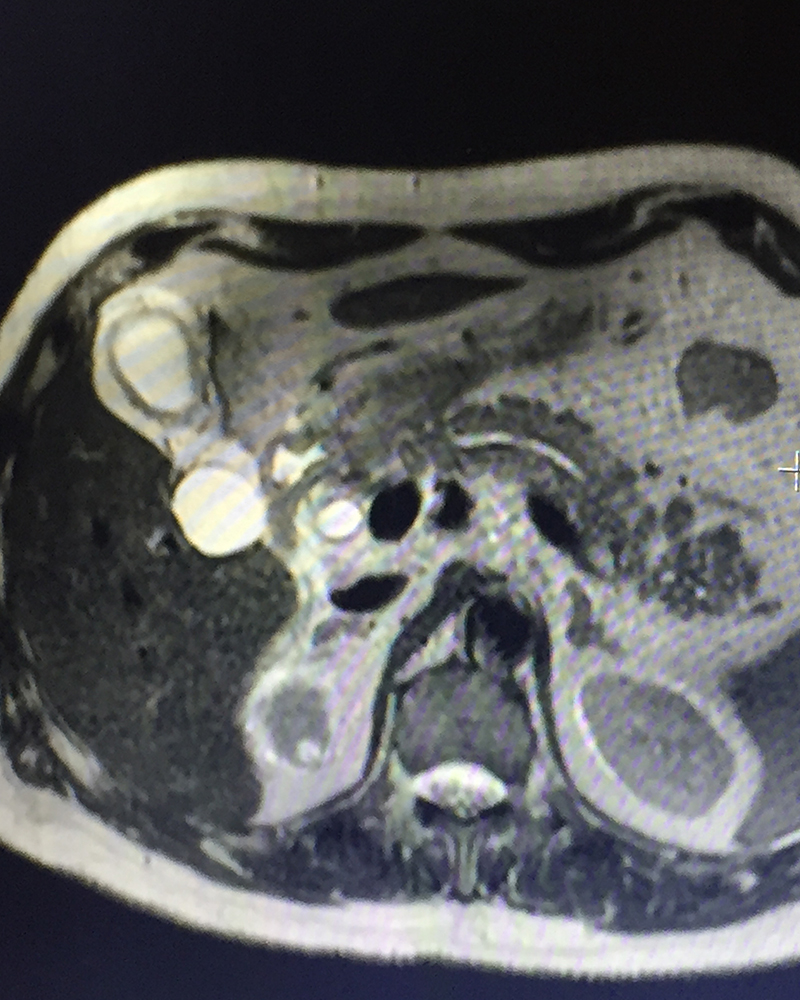

79 year old gentleman with diabetes, hypertension, cardiac problems, previous coronary bypass surgery and borderline renal function presented with acute abdominal pain in the right upper abdomen & periumbilical area, vomiting, abdominal bloating / distension and not passing gases. He had one episode of high grade fever too. Initial investigations (blood & abdominal sonography) showed evidence of infection (high leucocyte count & CRP), jaundice (raised bilirubin), biliary infection / inflammation – cholecystitis / cholangitis -- (raised SGOT / SGPT / alkaline phosphatase -- liver enzymes), mild pancreatitis (raised amylase / lipase –pancreatic enzymes) and worsening renal function (BUN / creatinine). The ultrasonography showed stones in the gall bladder with severe cholecystitis (gall bladder inflammation / swelling), large stones in the bile duct and pancreatitis (inflammation / swelling of pancreas). The patient was diagnosed with acute calculous cholecystitis, obstructive jaundice & cholangitis due to stones in the bile duct, acute biliary pancreatitis (pancreatitis caused by passage of stone / obstruction of mouth of the common channel of bile & pancreatic duct). The vomiting, dehydration & infection had caused acute injury to the already compromised kidney (due to diabetes & hypertension) leading to further worsening of the renal function. A MRCP (MRI examination of biliary / pancreatic ducts) & IV contrast MRI abdomen was done to confirm the diagnosis. The pancreatitis was fortunately mild on MRI.